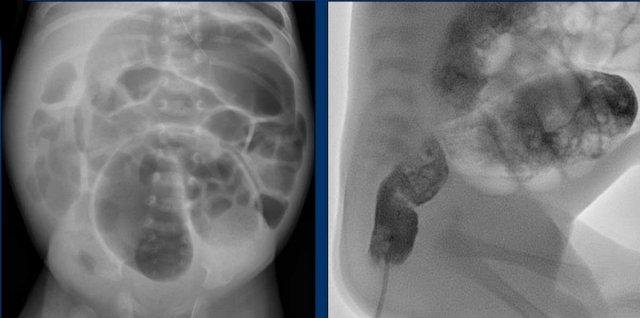

Hình ảnh

Tắc ruột ở trẻ sơ sinh mắc bệnh Hirschsprung.

Đại tràng sigma giãn to và không có hơi trong trực tràng.

Trên phim thụt tháo cản quang, đường kính trực tràng nhỏ hơn đại tràng sigma.

Tỷ lệ trực tràng/sigma <1 rất gợi ý bệnh Hirschsprung.

- Các vùng thấu quang dạng bong bóng do lactobezoar ở góc phần tư dưới phải ở trẻ mắc hội chứng cục sữa đông. Hình ảnh này có thể gây lo ngại về khí trong thành ruột (pneumatosis intestinalis).

- Siêu âm cho thấy thành ruột bình thường, không có khí trong thành ruột, nhưng có nội dung trong lòng ruột rõ ràng dày đặc.